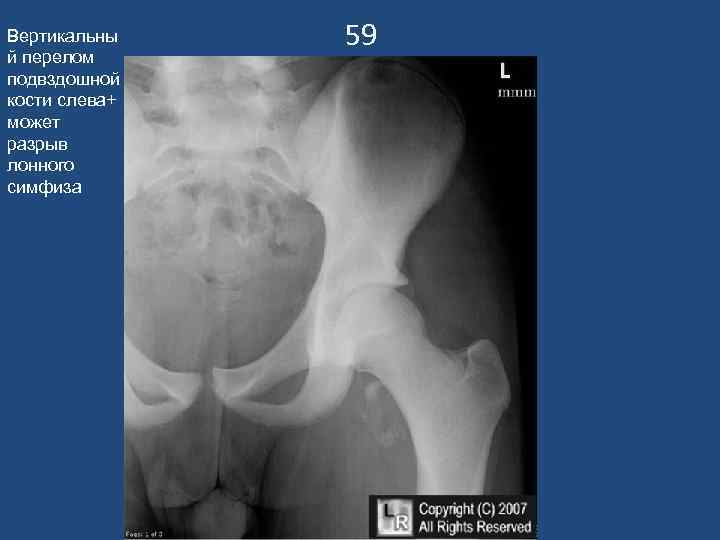

Вертикальны й перелом подвздошной кости слева+ может разрыв лонного симфиза 59